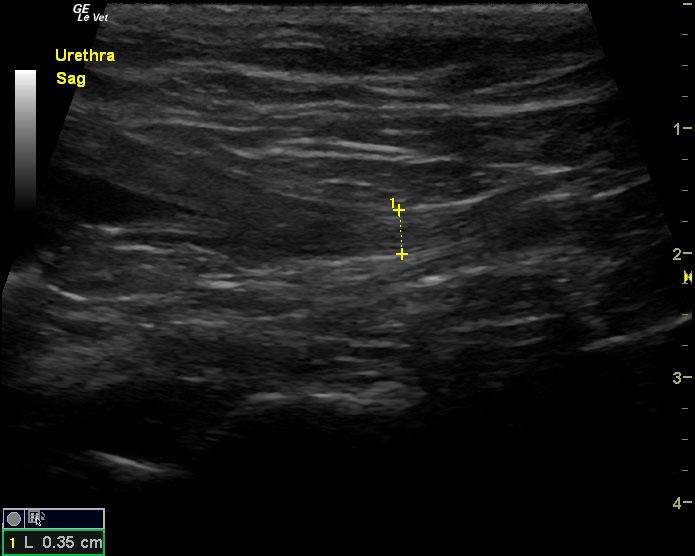

The urinary bladder in this patient revealed dependent debris that measured 2.1 cm in length. The bladder wall presented minor, apical ventral wall thickening. Suspended debris was also evident. The bladder wall thickening appeared to be concentric throughout with some loss of mural detail, and measured 0.4 cm at minor repletion. The pelvic urethra was also thickened. These images are most consistent with interstitial cystitis with minor potential for bladder lymphoma. The kidneys revealed largely normal size and structure; corticomedullary definition and ratio (cortex 1/3 of medulla) were essentially maintained with minor loss of curvilinear pattern. The cortices presented largely uniform texture with some echogenic changes that are not likely of clinical significance at this time.